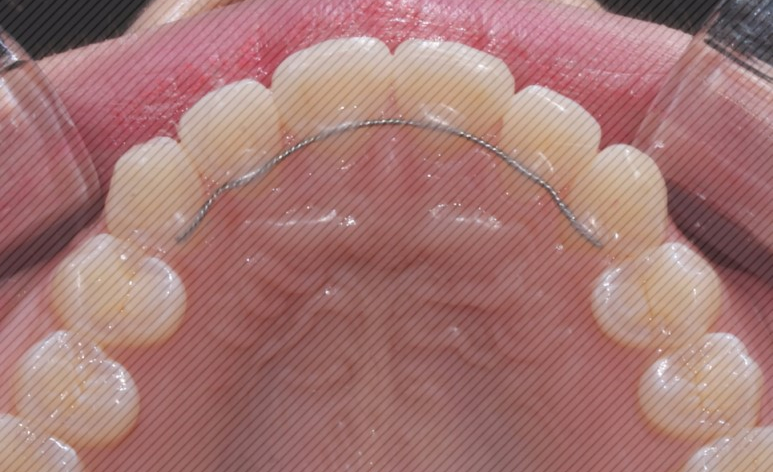

환자분의 상태는

상악 중절치와

앞니 절단연의 울퉁불퉁거림이

있는 편이어서

그 부분을 중점으로 치료하며

전체적인 배열에 맞게

2D교정 장치로

진행하기로 하였습니다.

동그라미가 되어있는 부분이

상악 우측 중절치로

치아가 입술 쪽으로 튀어나와

있는 상태입니다.

왼쪽 중절치와 겹쳐 보이고 있습니다.

2D치과는 화살표 부분의

절단연 (씹는면) 은

환자분의 요청에 따라

평평하게 연마하여

진행되었습니다.